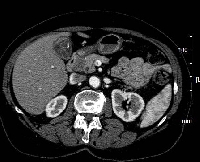

Πρόκειται για γυναίκα ασθενή 70 ετών, η οποία υποβλήθηκε σε αξονική τομογραφία για άτυπα γαστρεντερικά συμπτώματα, εμέτους και απώλεια βάρους. Διαπιστώθηκε συμπαγής μάζα του παγκρέατος, μεγέθους 3 εκατοστών, η οποία εντοπίζονταν στην κεφαλή του οργάνου και βρίσκονταν σε ικανή απόσταση από τα άνω μεσεντέρια αγγεία (εικόνα 1). Η ασθενής έλαβε 4 κύκλους προεγχειρητικής (neoadjuvant) χημειοθεραπείας (gemcitabine, cisplatine, erlotinib). Κατόπιν υποβλήθηκε σε επέμβαση Whipple's (εικόνα 2) με παγκρεατογαστροστομία (εικόνες 3, 4). Στο παρασκεύασμα (με και χωρίς αριστερή εκστροφή της χοληδόχου κύστης) φαίνεται η μάζα (εικόνες 5, 6).